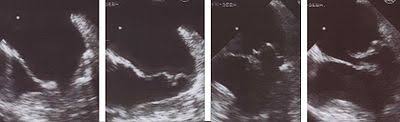

Durch eine Erweiterung der linken Herzkammer zB. Für Leute die weit von der Medizin entfernt sind klingt diese Aussage wie ein Kauderwelsch. Eine Mitralklappeninsuffizienz kann akut entstehen zum Beispiel infolge eines plötzlichen Chordaabrisses am Halteapparat der Mitralklappe mit akutem Prolaps schwerer Mitralklappeninsuffizienz und.

Patienten spüren Atemnot bei Belastung später auch in Ruhe. Herzrhythmusstörungen und Vorhofflimmern Blutgerinnsel im betroffenen Atrium verminderte Leistungsfähigkeit Atemnot sowie Ödeme bei Beteiligung der rechten Herzkammer sind charakteristische Symptome einer Mitralklappeninsuffizienz. Akute Mitralklappeninsuffizienz Eine akute Mitralklappeninsuffizienz verläuft meist fulminant mit Anzeichen einer akuten Herzinsuffizienz Lungenödem kardiogenem Schock und Multiorganschäden.